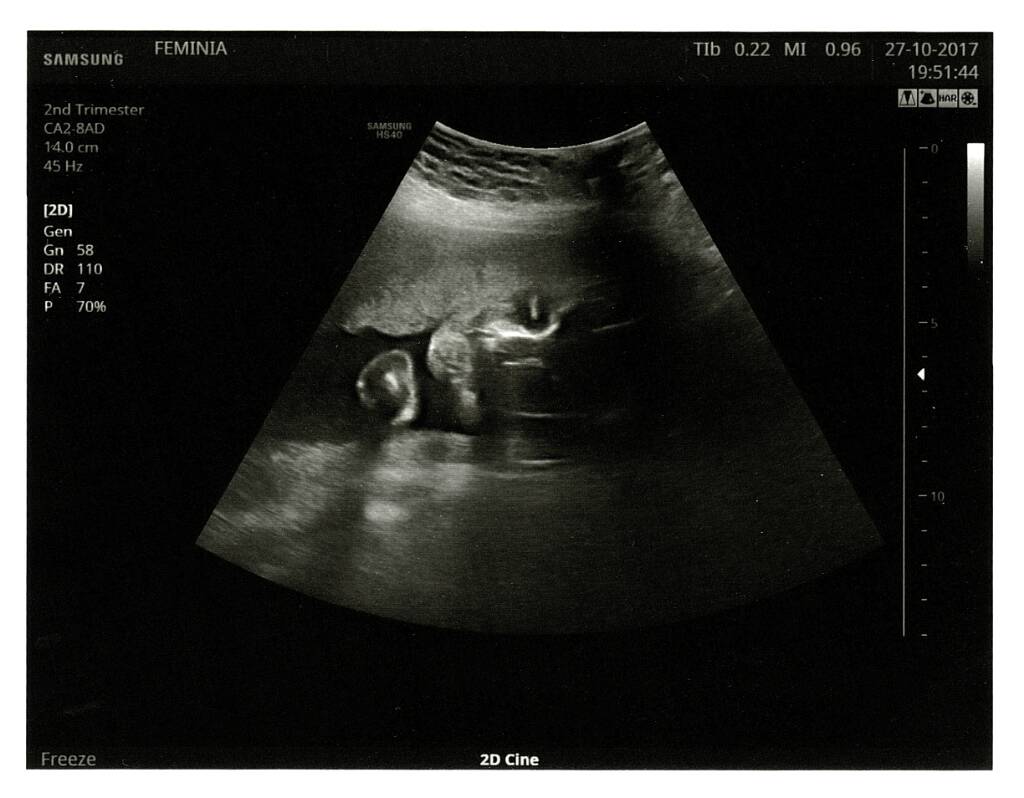

Ja po piątkowej wizycie mogę donieść tylko, że nie wiemy nic nowego [emoji14] uparciuch i tyle z tego naszego malucha. Mam się nie przejmować ddimerami, będą rosnąć i tak, ale w związku z przyjmowaną heparyną jesteśmy chronione. Jak to Pani doktor ujęła ddimerozy nie leczymy, bo to stan fizjologiczny. Jest to powszechne stanowisko w środowisku lekarskim. Ew. zwiększenie dawki dopiero po 30 tc. Zdziwiłam się też najnowszymi wytycznymi dot. podnoszenia dawek Euthyroxu, należy reagować dopiero gdy tsh skoczy do 4 [emoji44][emoji44][emoji44] na szczęście u mnie 1,5 więc 75 daje radę. Pozdrawiamy internetowe ciotki typowo Halloweenową fotką [emoji4]

Ja po piątkowej wizycie mogę donieść tylko, że nie wiemy nic nowego [emoji14] uparciuch i tyle z tego naszego malucha. Mam się nie przejmować ddimerami, będą rosnąć i tak, ale w związku z przyjmowaną heparyną jesteśmy chronione. Jak to Pani doktor ujęła ddimerozy nie leczymy, bo to stan fizjologiczny. Jest to powszechne stanowisko w środowisku lekarskim. Ew. zwiększenie dawki dopiero po 30 tc. Zdziwiłam się też najnowszymi wytycznymi dot. podnoszenia dawek Euthyroxu, należy reagować dopiero gdy tsh skoczy do 4 [emoji44][emoji44][emoji44] na szczęście u mnie 1,5 więc 75 daje radę. Pozdrawiamy internetowe ciotki typowo Halloweenową fotką [emoji4]